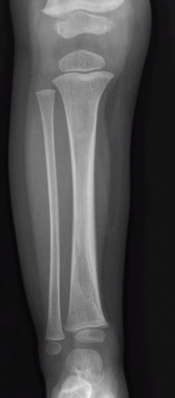

What’s the diagnosis? Gepost op 21 maart 20214 maart 2021 door netwerkvsseh What’s the diagnosis? By Dr. Michael Tom @emdaily.cooperhealth.org Dit delen: Delen op X (Opent in een nieuw venster) X Share op Facebook (Opent in een nieuw venster) Facebook Delen op LinkedIn (Opent in een nieuw venster) LinkedIn E-mail een link naar een vriend (Opent in een nieuw venster) E-mail Afdrukken (Opent in een nieuw venster) Print Vind-ik-leuk Aan het laden... Gerelateerd